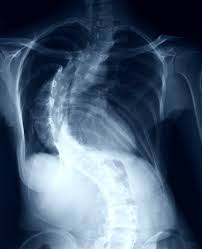

Scoliosis is derived from the Greek term meaning curvature. The Tether System is different from the other surgical treatments for scoliosis because the spine is still able to bend and flex rather than being fixed in place. At Shriners Hospitals for Children every scoliosis brace is customized to the individual patient to best address the severity and location of their spinal curve.

Instead of falling into normal alignment the vertebrae make an S- or C-shaped curve. Thank you for your interest in the Scoliosis Research Society. Specialists who are not members will not be identified.

People with scoliosis have a sideways curve in their spine that makes an S or C shape.